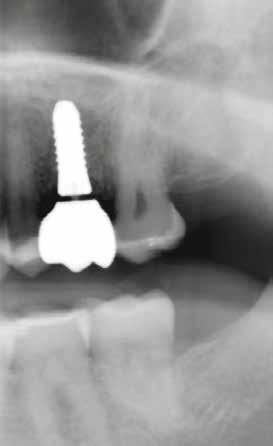

2. a–d ábra: PEEK zárócsavarok az implantátumokba helyezve, 1. eset (a). 2. eset (b). 3. eset (c), 4. eset (d). 3. a–b ábra: Röntgenfelvételek három hónap után (a) és a gyógyulási csavarok behelyezve (b, 1. eset). 4. a–b ábra: Röntgenfelvételek öt hónappal később (a) és a gyógyulási csavarok behelyezve (b, 2. eset). 2. táblázat: Az implantátum tulajdonságai.

6. a–b ábra: Röntgenfelvételek öt hónappal később (a) és a gyógyulási csavarok behelyezve (b, 4. eset).